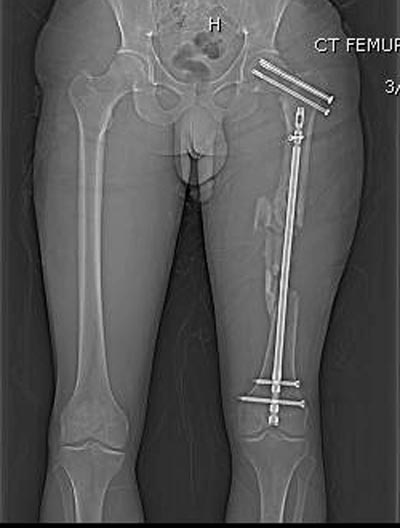

Здесь выставлен ренгенограммы больного, ему 21, травму получил в результате высокоскоростной погони на украденной машине, которая закончилась смертью трех остальных “боевых комрадов”. Начатую коллегой открытую операцию на шейке пришлось закончить мне, установкой винтов и ретроградной фиксацией бедра. Выписка в обычное сроки и наблюдался амбулаторно. Каждый раз напоминали о возможности осложнений ввиде несращения! По истечению 4 месяцев появились признаки варусной деформации. На СТ срезах несращение шейки и бедра. Риминг, замена на более толстый гвоздь и вальгусная остеотомия.

Сразу скажу, что пациент вчера (8.04) прооперирован - артротомия, остеосинтез мыщелков большеберцовой кости канюлированными винтами, открытая репозиция отломков бедренной кости, ретроградный БИОС, остеосинтез надколенника (центральных его отломков) спицами с проволочной петлей. Двухкратная попытка закрытой репозиции шейки на операционном столе после синтеза бедра - абсолютно неэффективна. Учитывая продолжительность и травматичность операции, шейка отложена на 2-й этап. Плечо наверное на 3-й (если вообще делать). Снимки постараюсь предоставить, но чуть позже.

КТ тазобедренного и коленного суставов сделали - картина удручающая, постараюсь выложить.